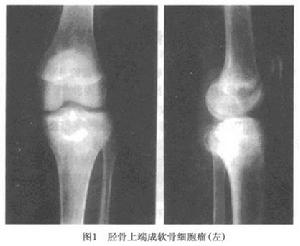

1.X線檢查 通常病變發生於長骨的骨骺內,呈圓形或橢圓形,直徑2~4cm低密度陰影 邊緣清晰,周圍有反應骨形成硬化緣,某些病灶可見點狀鈣化,相對應的骨幹可見連續的骨膜反應(圖1,2) 有時病變可伴有動脈瘤樣骨囊腫,X線片會顯示膨脹。成軟骨細胞瘤的X線表現的特點是在骨骺或骨性突起處有一位於中心或者偏心的溶骨性病變,其大小通常在5~6cm,病變界線清楚呈圓形或卵圓形。腫瘤周圍有一很細的硬化邊緣可將腫瘤與正常組織分開(圖1)。臨近的軟骨可以變薄或受到侵蝕。腫瘤可擴展至軟骨下骨,但很少進入關節間隙 有30%~50%的病例在病變中有鈣化灶。由於鈣化的程度不盡相同,有時需X線斷層或CT的幫助才能確定某些鈣化灶。約有30%的病例在鄰近的骨幹或乾骺端出現骨膜反應。軟組織出現包塊和並發病理性骨折者少見。

五、好發部位成軟骨細胞瘤常發生在長管狀骨的骨骺部位或骨骺突起部位,依次為股骨、肱骨和脛骨。在股骨近端,腫瘤可起源於骨骺或大粗隆,發生於肱骨近端的軟骨母細胞瘤常起源於肱骨大結節,在脛骨,常發生於脛骨近側端。大多數軟骨母細胞瘤位於膝、肩和髖關節周圍。原發在乾骺端或骨幹部位者少見。股骨(33%)、肱骨(20%)和脛骨(18%)為最好發部位。在肱骨及脛骨最常見是在近側端,而股骨遠、近側端發病相同。下肢發病較上肢多。其他長管狀骨,例如尺、橈骨、腓骨發病者不多見。在手、足骨上發病的成軟骨細胞瘤約占10%,特別是距骨及跟骨。骨骼其餘部位少見。典型的部位是位於關節周圍骨上。鄰近關節表現為類似原發滑膜炎過程,約有30%患者有關節滲出液。由於擴張性生長,軟骨母細胞瘤傾向於破壞生長軟骨,可從骨骺蔓延至鄰近的乾骺端。在一些特殊病例,軟骨母細胞瘤可發生於生長軟骨的對側,即可位於乾骺端。